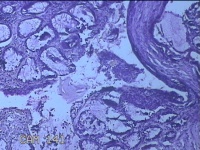

性别

男

年龄

40岁

临床诊断

混合痔

一般病史

反复肛门肿物突出15年。

标本名称

肛门肿物

大体所见

灰白暗红色肿物0.7x0.5x0.2cm一个,表面糜烂。

脱水、透明,浸蜡、脱蜡效果不佳,制片质量差。